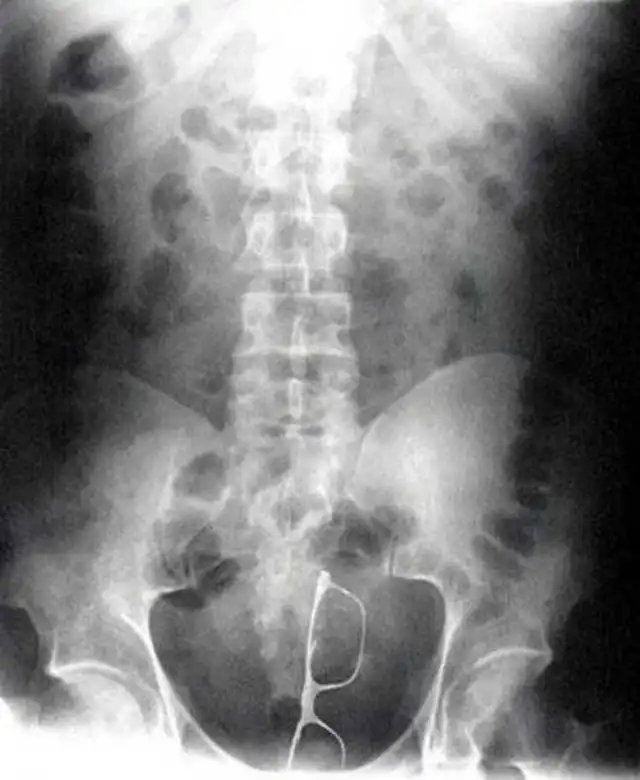

Все фотографии из этого поста действительно непросто объяснить. Странные выходки людей, необычные моменты, запечатленные на камеру, необъяснимые происшествия, к которым сложно подобрать рациональное объяснение, всё это и еще много других странностей в продолжении поста.